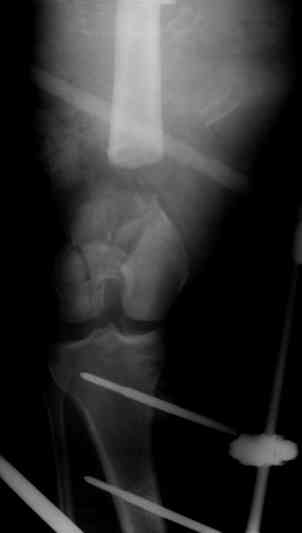

Разрешите рассказать о пациенте, которому мы фиксировали перелом такой конструкцией.

Больной 19 ти лет, пострадал в результате ДТП, пассажир мотоцикла. Получил открытый оскольчатый перелом н/3 левой бедренной кости 3a тип по Гастилло-Андерсену. При поступлении ПХО ран, фиксация стержневым аппаратом наружной фиксации. Лечение больного осложнилось развитием анаэробной флегмоны левого бедра. Лампасные разрезы, неоднократные некрэктомии, некротизировался участок диафиза левой бедренной кости на протяжении 15 см. Произведена резекция. 20.05.10- демонтаж АНФ, остеоситез левой бедренной кости гибридным циркулярно-монолатеральным стержневым дистракционным аппаратом наружной фиксации, остетомия левой бедренной кости в в/3. Сейчас начата дистракция в аппарате, проводится подготовка ран к аутодермопастике.

С уважением. Удачи!

5.jpg